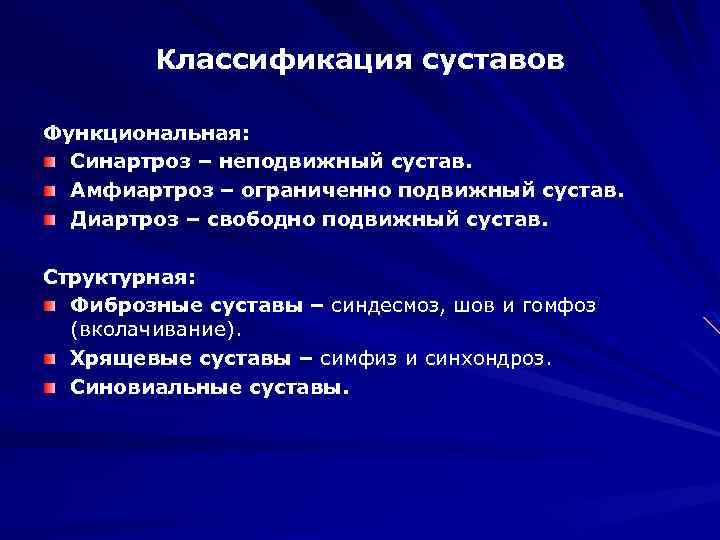

Структура и анатомия синдесмоза: научные иллюстрации